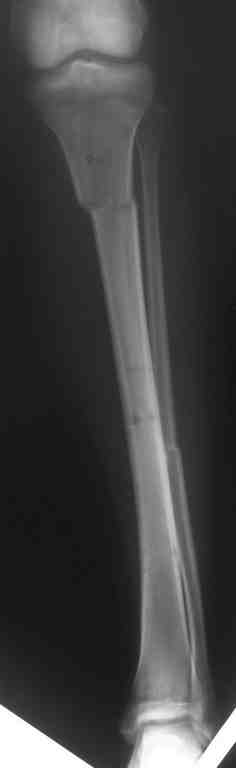

Выше представлены рентгенограммы открытого оскольчатого перелома нижней трети голени

X-rays of Compound Comminuted # Distal/3 Lt Tibia

Операционные снимки перед и после наложения аппарата Илизарова

In operation room before and after Ilizarov apparatus has been applied

Послеоперационные рентгенограммы

Postoperative X-rays

В нижнем ряду представлены рентгенограммы после окончательной репозиции.

And final reduction after Hexapod program has been finished